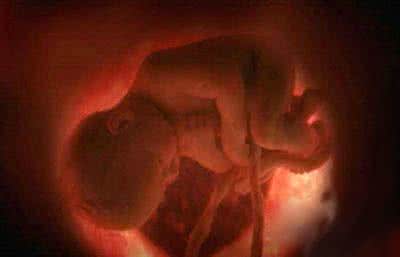

2016年8月底,市民邹某在某网站发帖称,在其孕检时,因宝安区妇幼保健院超声检查医生吕某某使用探头用力过度,导致其腹中胎儿死亡。该帖中多次用比较激烈的言语指向当事医生。

据介绍,经过中山大学法医鉴定中心鉴定,根据法医系统尸体解剖检验,邹某之女体表及内部器官未发现机械性损伤征象,故可排除机械性暴力作用致死。结合案情分析,邹某之女属未成熟儿,符合宫内窒息死亡。